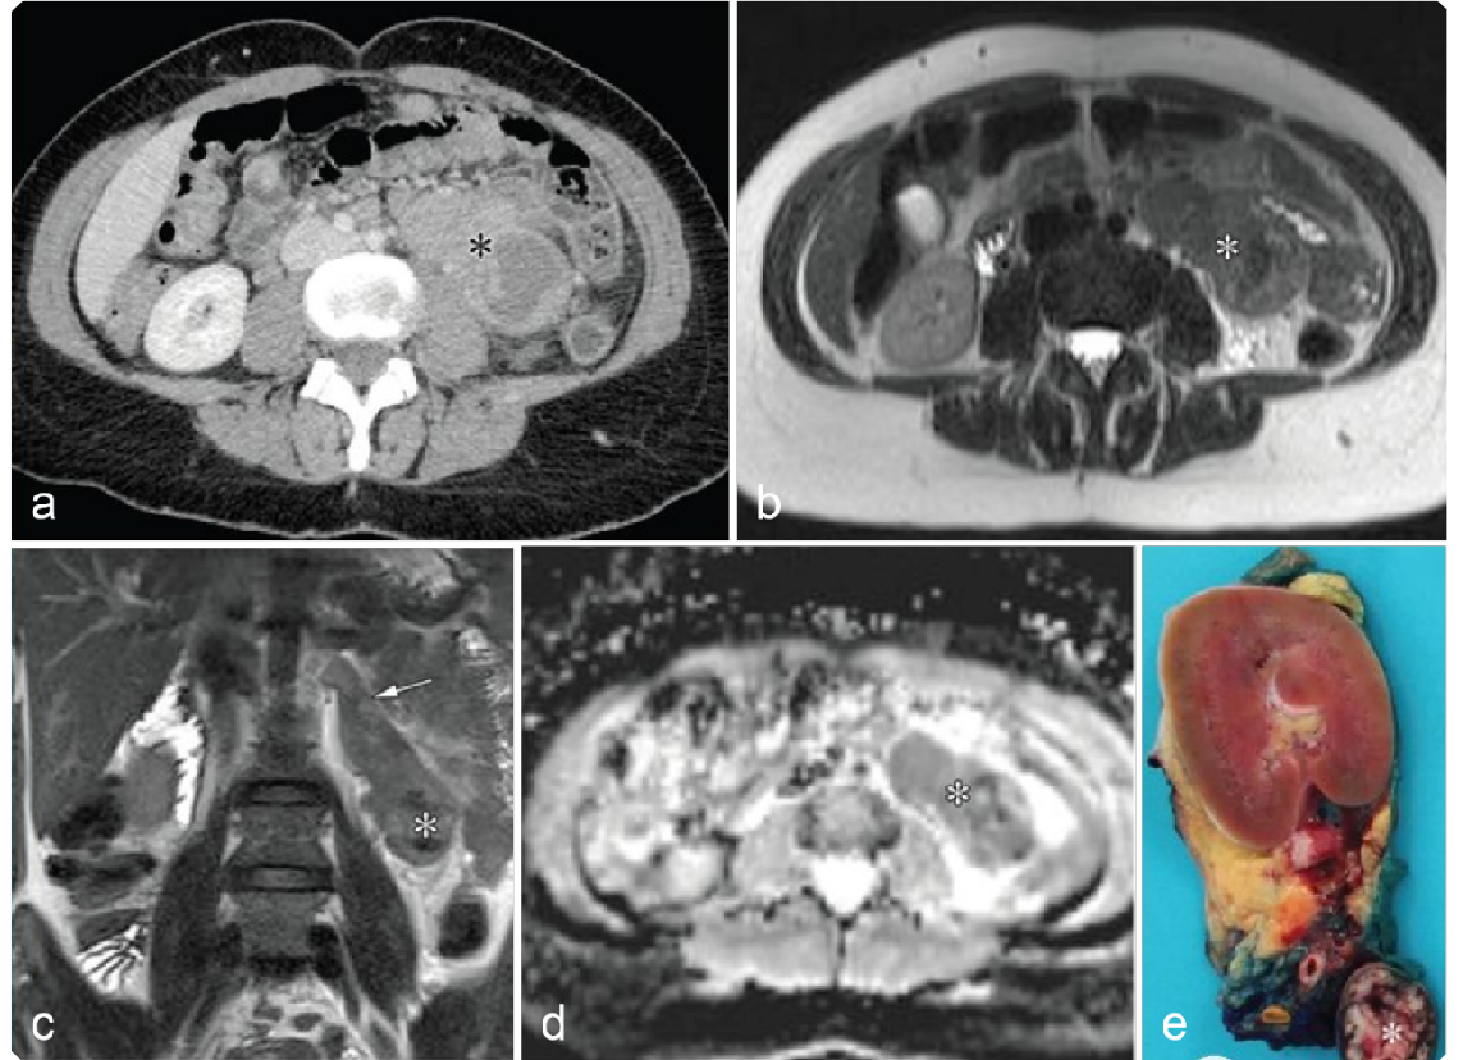

0a5fb18a3933294f8c258284440d05bf.png 病例 8:腹膜后(血管外)平滑肌肉瘤  46岁女性 腹膜后肿物不均质强化,病灶与前方下腔静脉、上方肾上腺及下方肾脏分界清晰,病灶侵犯右侧腰大肌。瘤内少量出血,不均质强化,弥散受限。大体病理显示瘤内出血、坏死;镜下:具有有丝分裂和核异型的梭形细胞。

0a6556b925dbc726a8c295b13d4e5389.png 病例 9:腹膜后(血管外)平滑肌肉瘤  64岁女性右侧腹膜后巨大软组织肿块,不均质强化侵犯肝脏(黑箭)及右肾(白箭)。大体病理显示肿瘤侵犯右肾,瘤内出血、坏死(*)。

5cda817c00c60fa04c459763294e72d0.png 病例 10:腹膜后(血管外)平滑肌肉瘤  66岁男性,腹痛3个月,食欲下降,体重减轻右肾周巨大不均质肿块,内见坏死区,未见侵犯右肾。大体病理显示肿瘤位于右肾下部,完全位于肾外,肿瘤切面呈棕白色轮辐状外观。